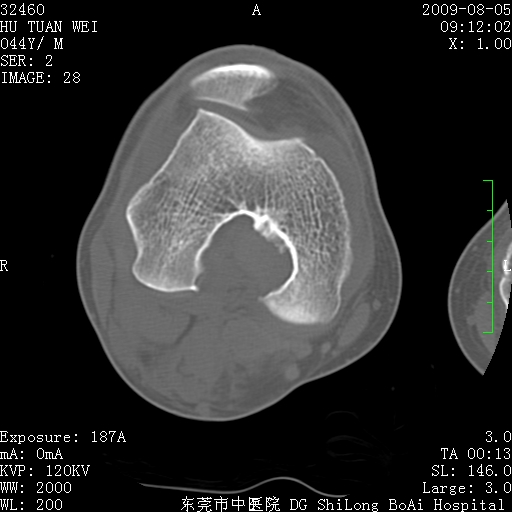

标题: CT21940:膝关节(有病理)

中年男性,膝韧带损伤术前检查!其他病史不清粗,不是我接手病人、且出院了!

1、股骨下段囊状膨胀性病变,边缘硬化明显,内多个残留骨棘呈多房型改变,囊腔密度较高无钙化,膝关节滑膜囊增厚,密度增高,关节腔少量积液。考虑:邻关节囊肿、退变性囊肿(软骨下囊肿)、着色性绒毛结节性滑膜炎、abc、骨巨、良性纤维组织细胞瘤等鉴。虽然年龄偏大,部位于骨端,但有外伤史,本人还是倾向于动脉瘤样骨囊肿(abc)可能性大。邻关节囊肿及软骨下囊肿次之考虑。

2、胫骨髁间棘撕脱骨折,交叉韧带损伤可能;

3、关节退行性改变。

病理结果:色素沉着绒毛结节性滑膜炎

感谢反馈病理结果!本病为慢性关节病变。以关节滑膜高度增生、绒毛结节形成伴含铁血黄素趁着为特点。病因:有炎症、肿瘤、外伤关节出血、代谢障碍、变态反应及感染等学说。增强扫描呈关节腔内单个或多个强化的软组织结节影或滑膜不规则增厚伴关节积液为本病的特征性表现。